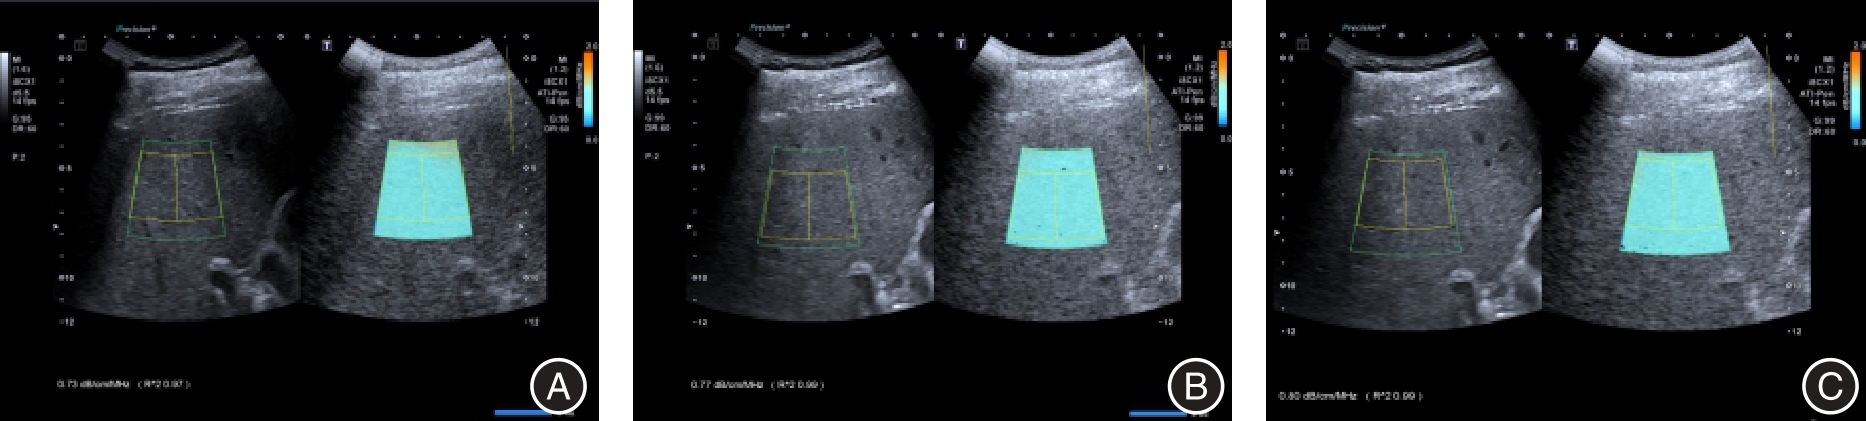

目的 探讨磁共振成像-弥散加权成像(MRI-DMI)联合超声声衰减成像(ATI)诊断脂肪肝背景下< 2 cm局灶结节性病变的价值。 方法 回顾性分析2022年6月至2023年6月河南大学淮河医院收治的68例脂肪肝合并< 2 cm局灶结节性病变的临床资料,所有患者均接受MRI检查、病理学检查与ATI检查。根据脂肪肝病变程度不同将68例患者分为重度组(n = 24)、中度组(n = 27)、轻度组(n = 17)。对比不同局灶节性病变患者的表观扩散系数(ADC)值、声衰减系数(AC)值与临床资料,对比不同脂肪肝病变程度患者的ADC值、AC值与临床资料,采用Pearson分析相关性,分析MRI-DWI联合AC值对脂肪肝合并< 2 cm局灶结节性病变为恶性的诊断价值。 结果 病理学诊断结果显示,68例患者中,41例为良性结节,27例为恶性结节。良性结节组与恶性结节组低密度脂蛋白胆固醇(LDL-C)、年龄、三酰甘油(TG)、性别、总胆固醇(TC)、高密度脂蛋白胆固醇(HDL-C)对比差异无统计学意义(P > 0.05)。轻度组、中度组、重度组TG、年龄、HDL-C、性别、TC、LDL-C比较差异无统计学意义(P > 0.05)。恶性结节组不同b值下的ADC值低于良性结节组(P < 0.05),恶性结节组AC值高于良性结节组(P < 0.05)。重度组不同b值下的ADC值低于轻度组、中度组(P < 0.05),中度组不同b值下的ADC值低于轻度组(P < 0.05),重度组AC值高于轻度组、中度组(P < 0.05),中度组AC值高于轻度组(P < 0.05)。不同b值下的ADC值与脂肪肝病变程度均呈负相关(P < 0.05),与TG、HDL-C、TC及LDL-C无关(P > 0.05);AC值与脂肪肝病变程度呈正相关(P < 0.05),与HDL-C呈负相关(P < 0.05),与TG、TC及LDL-C无关(P > 0.05)。MRI-DWI、AC值及二者联合诊断脂肪肝合并< 2 cm局灶结节性病变为恶性的曲线下面积(AUC)值分别为0.775、0.773、0.909(P < 0.05),且二者联合的AUC值更高(P < 0.05)。 结论 MRI-DWI、ATI在鉴别诊断脂肪肝背景下< 2 cm局灶结节性病变良恶性中具有重要价值,且二者联合具有更高的诊断价值。

Objective To investigate the value of magnetic resonance image-diffusion weighted imaging (MRI-DMI) combined with attenuation imaging (ATI) in the diagnosis of focal nodular lesions < 2 cm in the background of fatty liver. Methods The clinical data of 68 patients with fatty liver complicated with focal nodular lesions < 2 cm were retrospectively analyzed from June 2022 to June 2023 in Huaihe Hospital of Henan University. All patients underwent MRI, pathology and ATI examination. According to the degree of fatty liver disease, 68 patients were divided into severe group (n = 24), moderate group (n = 27) and mild group (n = 17). The apparent diffusion coefficient (ADC) and acoustic attenuation coefficient (AC) values of patients with different focal lesions were compared with clinical data, and the ADC values and AC values of patients with different fatty liver lesions were compared with clinical data, and the correlation was analyzed by Pearson. To analyze the value of MRI-DWI combined with AC value in the diagnosis of malignant fatty liver disease with focal nodular disease < 2 cm. Results Pathological diagnosis showed that 41 of the 68 patients were benign and 27 were malignant. There were no significant differences in low density lipoprotein cholesterol (LDL-C), age, triglyceride (TG), sex, total cholesterol (TC) and high density lipoprotein cholesterol (HDL-C) between benign nodule group and malignant nodule group (P > 0.05). There was no difference in TG, age, HDL-C, sex, TC and LDL-C among mild, moderate and severe groups (P > 0.05). The ADC value of malignant nodule group was lower than benign nodule group under different b values (P < 0.05), and the AC value of malignant nodule group was higher than that of benign nodule group (P < 0.05). ADC value under different b values in the severe group was lower than mild and moderate groups (P < 0.05), ADC value under different b values in the moderate group was lower than mild group (P < 0.05), AC value in the severe group was higher than mild and moderate groups (P < 0.05), and AC value in the moderate group was higher than mild group (P < 0.05). ADC values at different b values were negatively correlated with the degree of fatty liver disease (P < 0.05), but not with TG, HDL-C, TC and LDL-C (P > 0.05). AC was positively correlated with the degree of fatty liver disease (P < 0.05), negatively correlated with HDL-C (P < 0.05), but not with TG, TC and LDL-C (P > 0.05). The area under the curve (AUC) values of MRI-DWI, AC and their combination in the diagnosis of fatty liver complicated with focal nodule disease < 2 cm into malignancy were 0.775, 0.773 and 0.909, respectively (P < 0.05), and the AUC value of the combination was higher (P < 0.05). Conclusion MRI-DWI and ATI have important value in the differential diagnosis of benign and malignant lesions of focal nodular lesions < 2 cm in the background of fatty liver, and the combination of MRI-DWI and ATI has higher diagnostic value.